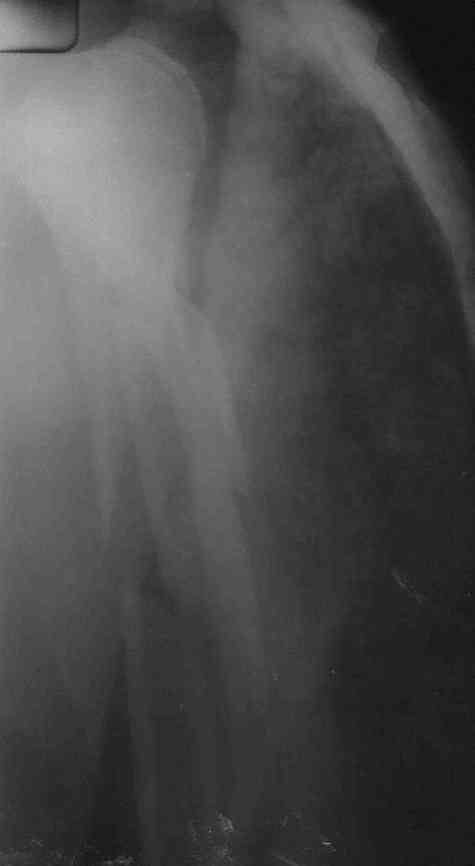

Re: Многооскольчатый перелом плечевой кости в В/3

Немножко переделал повязку с отведением, подправил, вот что получилось.

Перелом внутрисуставной, Вы уверены на счет Сармиенто? На первичном снимке не видно было перелома головки.

В наших условиях выбрали бы закрытое штифтование проксимальным гвоздем для плеча T2 Stryker. Голоку предварительно бы фиксировали спицами вне траектории гвоздя, чтобы не разобщить отломки.

Чтобы помочь определиться с выбором, и уточнить особенности выбранного варианта, надо знать, какие варианты доступны на месте.